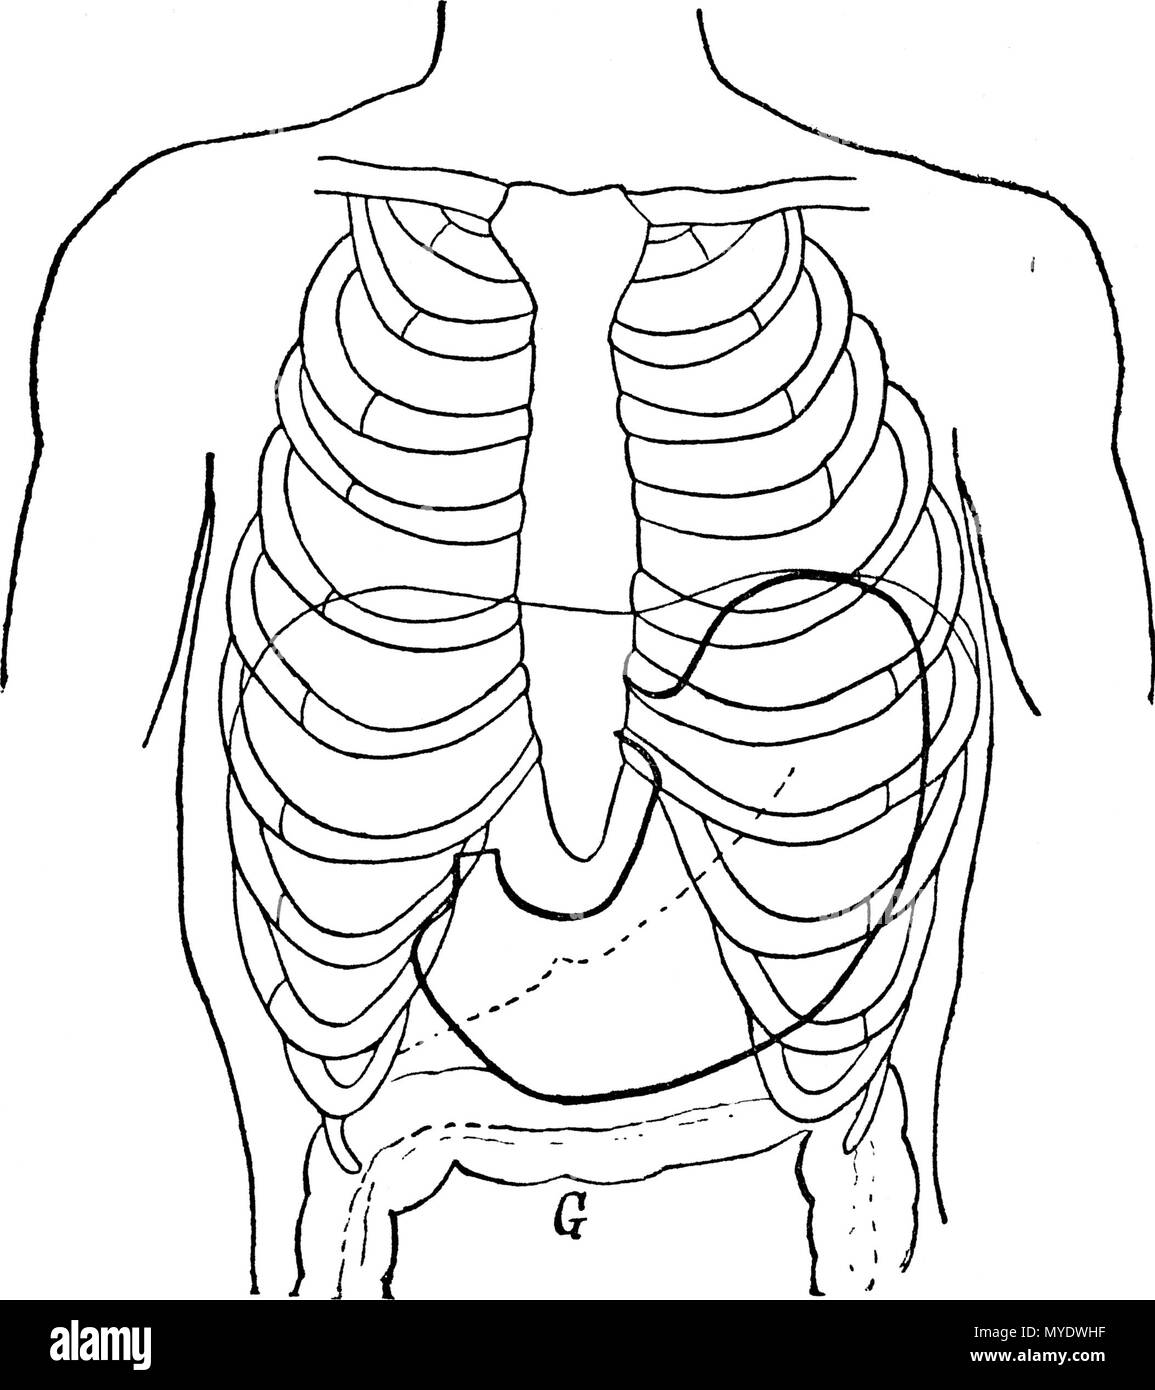

. Français : Figure 1 (d'après Boas); THORAX ET ESTOMAC NORMAUX; - - - - - - Bord inférieur du foie. Diaphragme. G Gros intestin. English: Figure 1 (according to Boas); NORMAL THORAXES AND STOMACH; - - - - - - lower Edge of the liver Diaphragm. G Large intestine . 1892. Le dr Eugène Chapotot 169 EstomacCorset page017 Stock Photohttps://www.alamy.com/image-license-details/?v=1https://www.alamy.com/franais-figure-1-daprs-boas-thorax-et-estomac-normaux-bord-infrieur-du-foie-diaphragme-g-gros-intestin-english-figure-1-according-to-boas-normal-thoraxes-and-stomach-lower-edge-of-the-liver-diaphragm-g-large-intestine-1892-le-dr-eugne-chapotot-169-estomaccorset-page017-image189004859.html

. Français : Figure 1 (d'après Boas); THORAX ET ESTOMAC NORMAUX; - - - - - - Bord inférieur du foie. Diaphragme. G Gros intestin. English: Figure 1 (according to Boas); NORMAL THORAXES AND STOMACH; - - - - - - lower Edge of the liver Diaphragm. G Large intestine . 1892. Le dr Eugène Chapotot 169 EstomacCorset page017 Stock Photohttps://www.alamy.com/image-license-details/?v=1https://www.alamy.com/franais-figure-1-daprs-boas-thorax-et-estomac-normaux-bord-infrieur-du-foie-diaphragme-g-gros-intestin-english-figure-1-according-to-boas-normal-thoraxes-and-stomach-lower-edge-of-the-liver-diaphragm-g-large-intestine-1892-le-dr-eugne-chapotot-169-estomaccorset-page017-image189004859.htmlRMMYDWHF–. Français : Figure 1 (d'après Boas); THORAX ET ESTOMAC NORMAUX; - - - - - - Bord inférieur du foie. Diaphragme. G Gros intestin. English: Figure 1 (according to Boas); NORMAL THORAXES AND STOMACH; - - - - - - lower Edge of the liver Diaphragm. G Large intestine . 1892. Le dr Eugène Chapotot 169 EstomacCorset page017